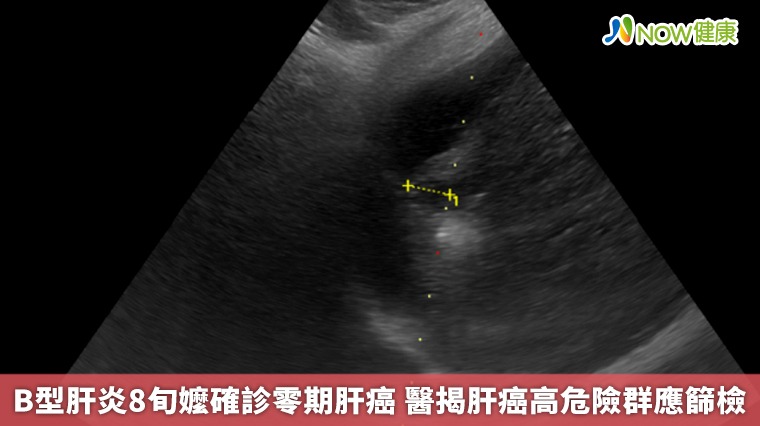

▲台北慈濟醫院胃腸肝膽科醫師鄭煜明提醒,肝臟疾病通常在初期難以發現,容易錯過治療佳機,建議45歲以上民眾終生主動接受一次B、C型肝炎篩檢。(圖/台北慈濟醫院提供)

根據臨床數據,零期肝癌治療後平均存活率超過10年以上,若延誤至第二期則縮短為約5年,第三期降至2.5年,若已轉移,存活時間僅剩半年。「在第零期使用電燒治療普遍可根治,不需要化療,已經有遠處轉移才會考慮使用免疫療法及標靶治療。」鄭煜明醫師解釋,電燒治療是透過超音波導引定位,使用電極產生電流,造成離子震動產生超過60度的熱能氣化腫瘤,比起手術能更完整保留健康的肝臟組織。